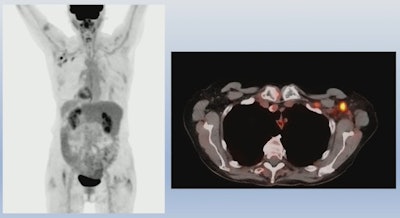

An example of PET/CT imaging from the study of a cancer patient who received the Pfizer-BioNTech COVID-19 vaccine showing FDG radiotracer uptake in the shoulder (left) and axial lymph node activity in the fused PET/CT image (right). Image courtesy of Dr. Mehemet Adin.According to the analysis, patients receiving the Pfizer-BioNTech and Moderna vaccines had similar incidences of reactive axillary lymph nodes in the first 20 days after the second dose (44% for the first 10 days for both groups, and 26% vs. 20% for days 10 to 20). However, Moderna recipients had higher incidences after 20 days than patients who received the Pfizer-BioNTech vaccine (4% vs. 15%).